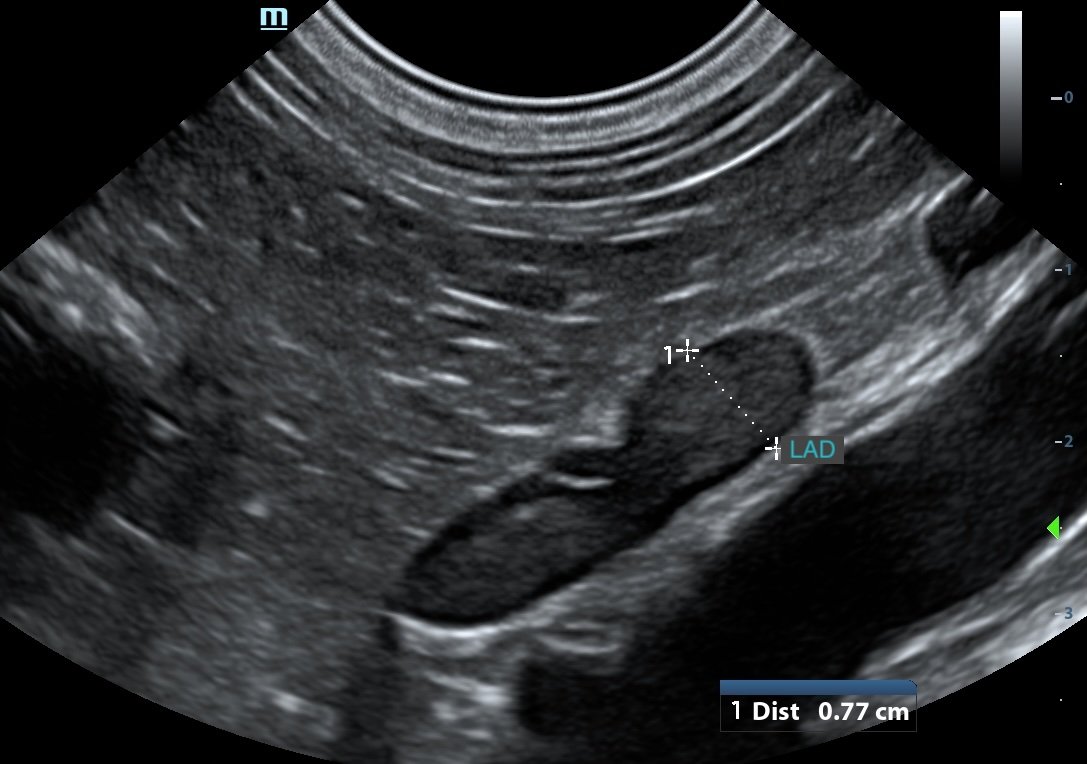

WATCH HOW IT ACTUALLY CAN LOOK IN PRACTICE

• reliably locate adrenal glands using consistent anatomical landmarks

• recognise normal vs abnormal with more confidence